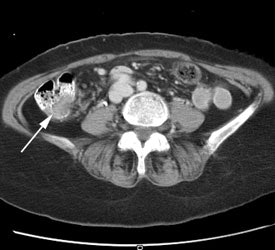

Initial staging for colorectal carcinoma: The patient below presented for evaluation of colorectal carcinoma. The CT scan demonstrated a large liver mass (red arrows) compatible with metastatic disease. The patient's cecal mass (black arrow on PET scan) was not detected on the CT study (white arrow). No other lesions were identified on the PET scan. |

|